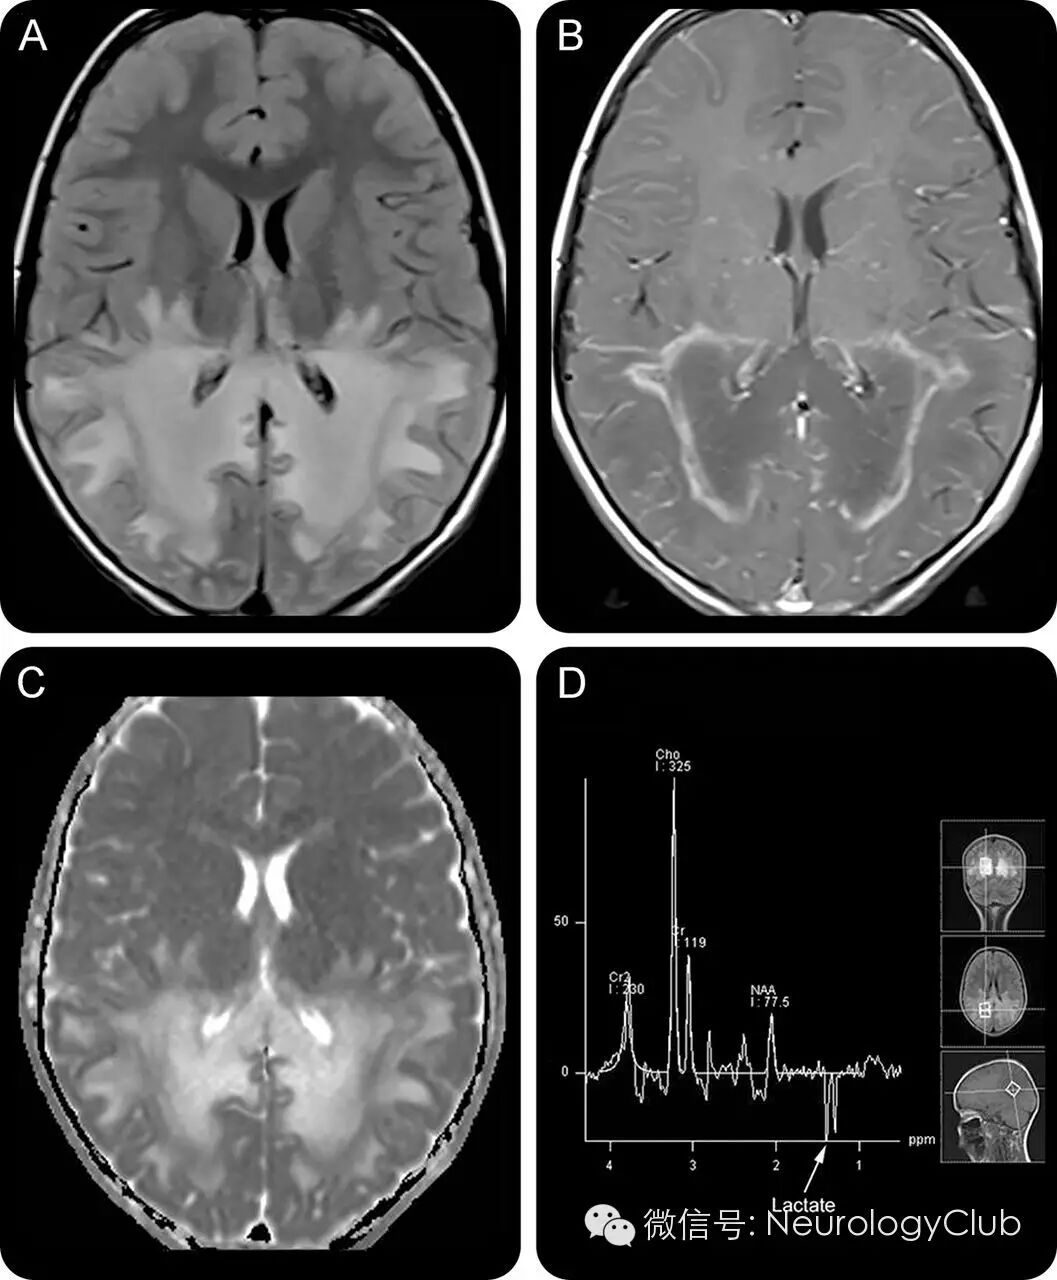

6岁男孩,进行性言语理解障碍,学习成绩下降,斜视伴视觉缺损4月。一般查体提示中度低血压以及皮肤色素沉着。神经系统查体提示理解困难,双眼视力下降,共轭凝视不良,双侧辨距不良,步态不稳。脑脊液蛋白升高(1.82g/L)。头颅MRI提示大脑后部和脑干异常信号。清晨皮质醇水平降低(21nM)。促肾上腺皮质激素兴奋试验证实肾上腺功能不全。极长链脂肪酸分析提示C26:0/C22:0和C24:0/C22:0比值升高。神经遗传学检测提示ABCD1基因突变。

(A:黑水像提示大脑半球后部对称融合性白质高信号病灶;B-C:T1增强可见对称性的线状强化,被认为是中间炎症区,其在黑水像和ADC上信号较其余病灶要低;D:MRS提示NAA下降,Cho升高,可见乳酸峰)

本病特征性的影像学改变是MRI可见双侧顶枕区白质对称分布的蝴蝶状长T1长T2信号,早期即可有胼胝体压部受累,并将两侧病灶连为一体。增强检查时能发现病灶周围可呈镶边样强化;如果病变进一步进展,病灶的累及范围可以由脑组织后部向前部发展(逐一累及枕、顶、颞、额叶)。脑干受累表现为脑干前外方双侧对称性点状或条形T1WI低信号、T2WI高信号,此征象在ALD病人较常见,而在其他脑白质病变中少见,有助于脑白质病变的鉴别诊断。MRI可基本反映ALD的病理分区:中央区T1WI呈更低信号,T2WI呈更高信号,增强扫描不强化。中间区T1WI呈稍低信号,T2WI呈高信号,增强扫描呈环状强化。外周区T1WI信号改变不明显,呈等信号,T2WI呈高信号,相当于T2WI所示病变范围超过T1WI的部分。有无强化与病情间存在明显相关性,非活动期病灶无强化,病灶强化提示处于活动期,病变多进一步恶化。晚期异常信号区扩大,增强后无强化,多伴有脑萎缩。